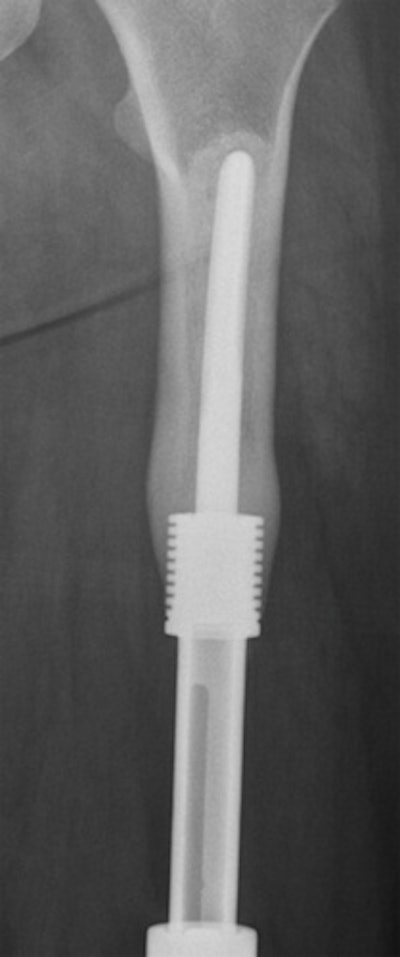

These images show treatments for osteosarcoma in a dog. Left: Radius and ulna custom modular endoprosthesis with hydroxyapatite collars and carpal arthrodesis. Right: Distal tibia custom modular endoprosthesis with hydroxyapatite collar and tarsal arthrodesis. Images courtesy of Dr. Noel Fitzpatrick.Synthetic cartilage

Fitzpatrick described how he operated on a dog with an osteosarcoma in the distal radius by implanting a custom endoprosthesis and the dog recovered and ran around, and is still running more than two years later. "Why is this relevant to humans?" he asked. "Well you can do bigger dogs with special collars on the end of the metal and on to these ends the bone physically grows," he explained.

"In the tibia or the radius, you can see the bone growing down around the end of the endoprosthesis," he added, showing radiographic images of the hydroxyapatite collar on the end of endoprostheses in the canine tibia, radius, and ulna (see images).